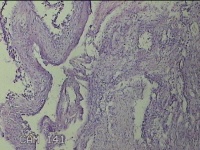

左卵巢囊肿

性别

女

年龄

47岁

临床诊断

左附件囊肿

一般病史

不规则阴道流血20余天。

标本名称

大体所见

灰白暗红色囊壁样组织4.3x1.3x0.3cm一块,表面光滑,因已切开,囊内容物已流失,囊壁厚0.1cm。

良性病变。